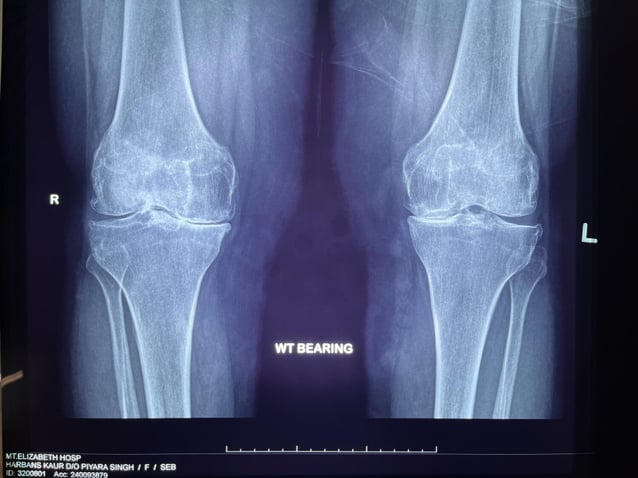

WT-bearing

Bowleggedness-knock-knees

Arthritis is a chronic condition where the cartilage - the smooth, protective tissue in your joints -wears out over time. This loss of cushioning is often joined by changes in the meniscus and the alignment of the knee, making it harder for the joint to move smoothly. As some parts of the knee wear out faster than others, the joint can become misaligned. Some people may become bow-legged, while others become knock-kneed. These changes can make it difficult to fully straighten or bend the knee, leading to pain and stiffness. Over time, this affects the way you walk and move, increasing the risk of falls, especially in older adults. Living with arthritis can feel discouraging, but understanding these changes is the first step to managing the condition and staying active.

Unfortunately, patients with arthritis may experience persistent pain, stiffness and difficulty with daily activities if they have end-stage arthritis which is not improving with conservative techniques. In this case, X-rays or an MRI scan may show structural changes and degeneration in their knees.